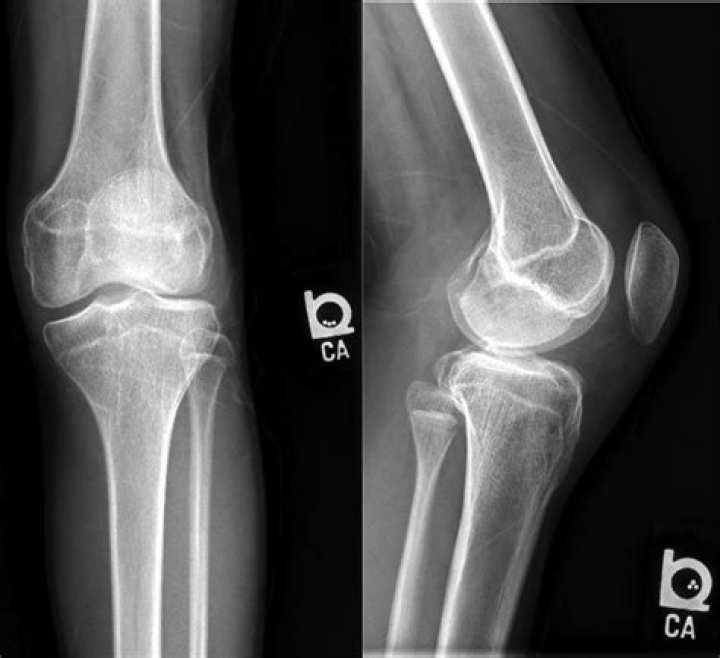

Owing to the characteristic soft-tissue calcifications of tumoral calcinosis, CT plays a primary role in diagnosis. In cases of advanced disease, the condition may be identified on radiographs. MRI is often performed after CT to evaluate for spinal cord signal abnormalities and for presurgical planning.